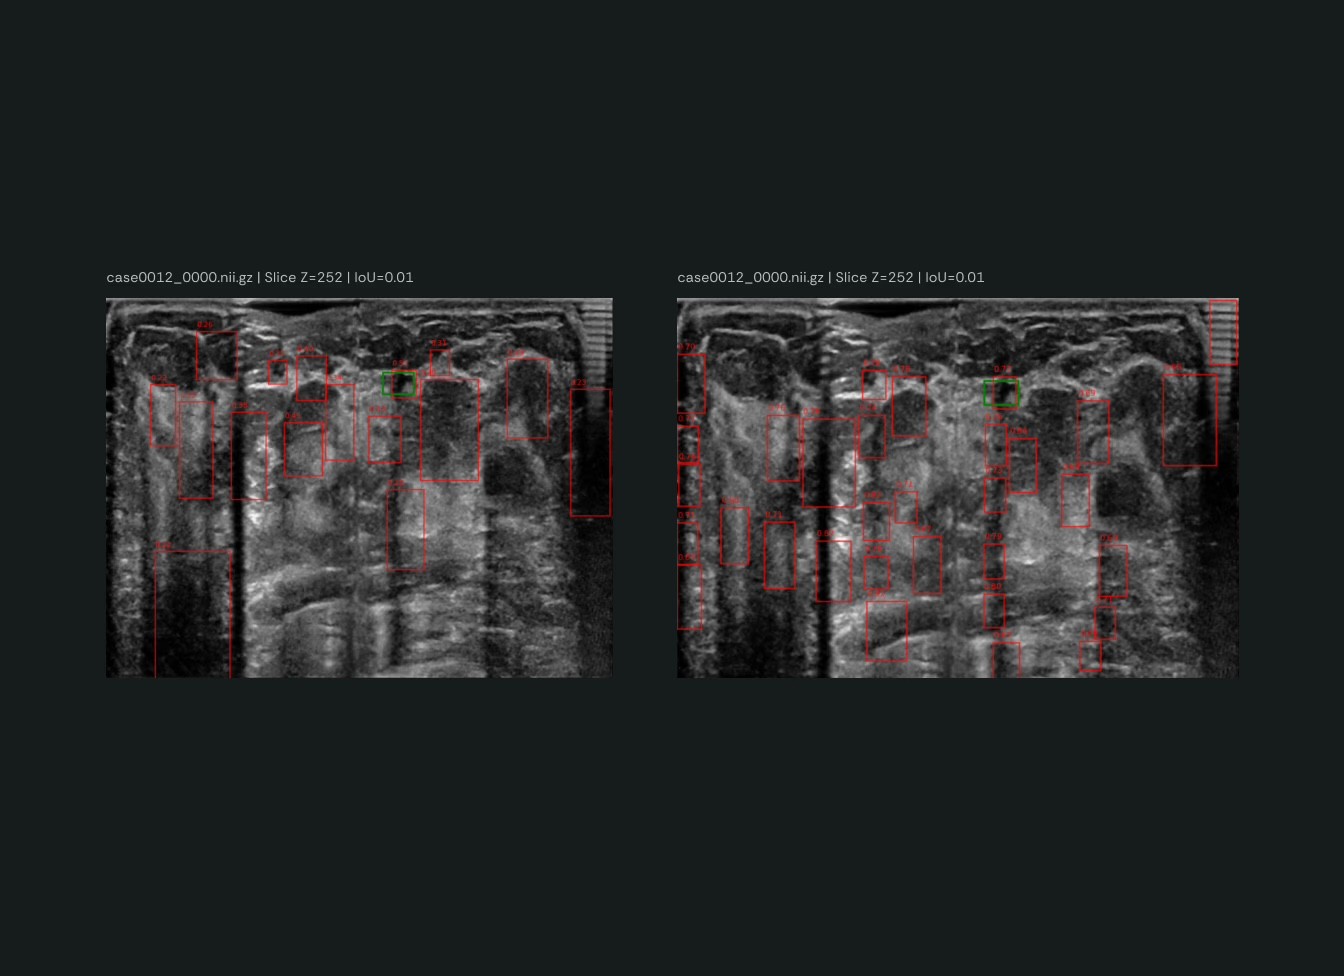

We introduced targeted modifications to the learning process — including hyperparameter changes within the focal loss function and experiments to assess their contribution.

As a result, we:Boosted model accuracy from 70% to 90% (a 28.6% relative improvement)

Achieved a 28.7% reduction in false detections

By analyzing false positives from both the original iSono model and our best-performing approach, we identified artifacts in images as a key source of noise — and proposed R&D ideas such as a model that simultaneously predicts artifacts and potential lesions to better discriminate between them.